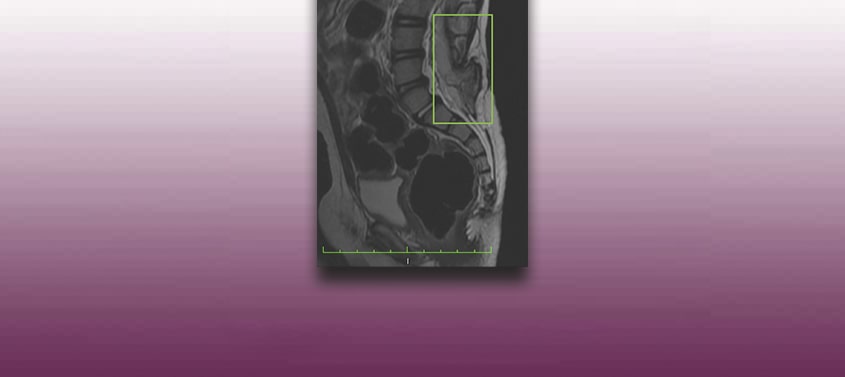

Midollo ancorato con spina bifida- meningocele o mielomeningocele- o Tethered cord Syndrome

Ultimo aggiornamento: 27/06/2019, Dott. Miguel B. Royo Salvador, nº. Ordine 10389. Neurochirurgo e Neurologo. Definizione In condizioni normali, il midollo spinale si trova collegato al canale vertebrale solo mediante i legamenti dentati e il filum terminale, un legamento che unisce il cono midollare con le prime vertebre del coccige. Quando invece la mobilità del […]